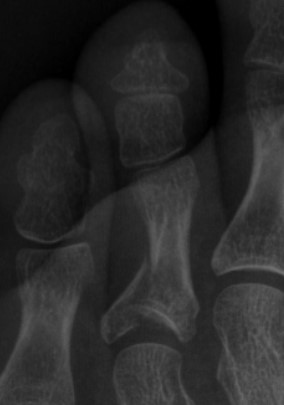

족무지의 경우 근위지골과 원위지골 2개로 이루어져 있으며, 소족지의 경우 근위지골, 중위지골, 원위지골 3개의 뼈로 이루어져 있는데, 근위지골의 골절이 중위지골, 원위지골의 골절보다 흔하다. 보행 시 힘을 족무지에 주게 되기 때문에 임상적으로 족무지 골절이 소족지 골절보다 더 중요하다.

그림 1. 제 4 발가락 근위지골의 관절을 침범한 골절

- 진단 단순 방사선 영상 검사를 통해 골절을 진단한다. 불완전 골절 등 정도가 심하지 않은 경우 초기 검사에서 발견되지 않을 수 있으므로 1~2주뒤 반복 촬영해서 확인해보는 것이 좋다. 신체검진에서도 해당부위의 뚜렷한 압통이 지속된다면 골절을 의심하게 된다. - 검사 신체검진이나 단순 방사선 영상 검사 외에 추가적인 검사가 반드시 필요한 경우는 흔치 않다. 그러나 드물게 증상이 전형적인 족지 골절의 양상이 아니거나 적절한 치료에도 증상 호전이 없는 경우, 다른 질환과의 감별 진단을 위하여 정밀 검사(CT, MRI) 등을 시행하는 경우도 있다.